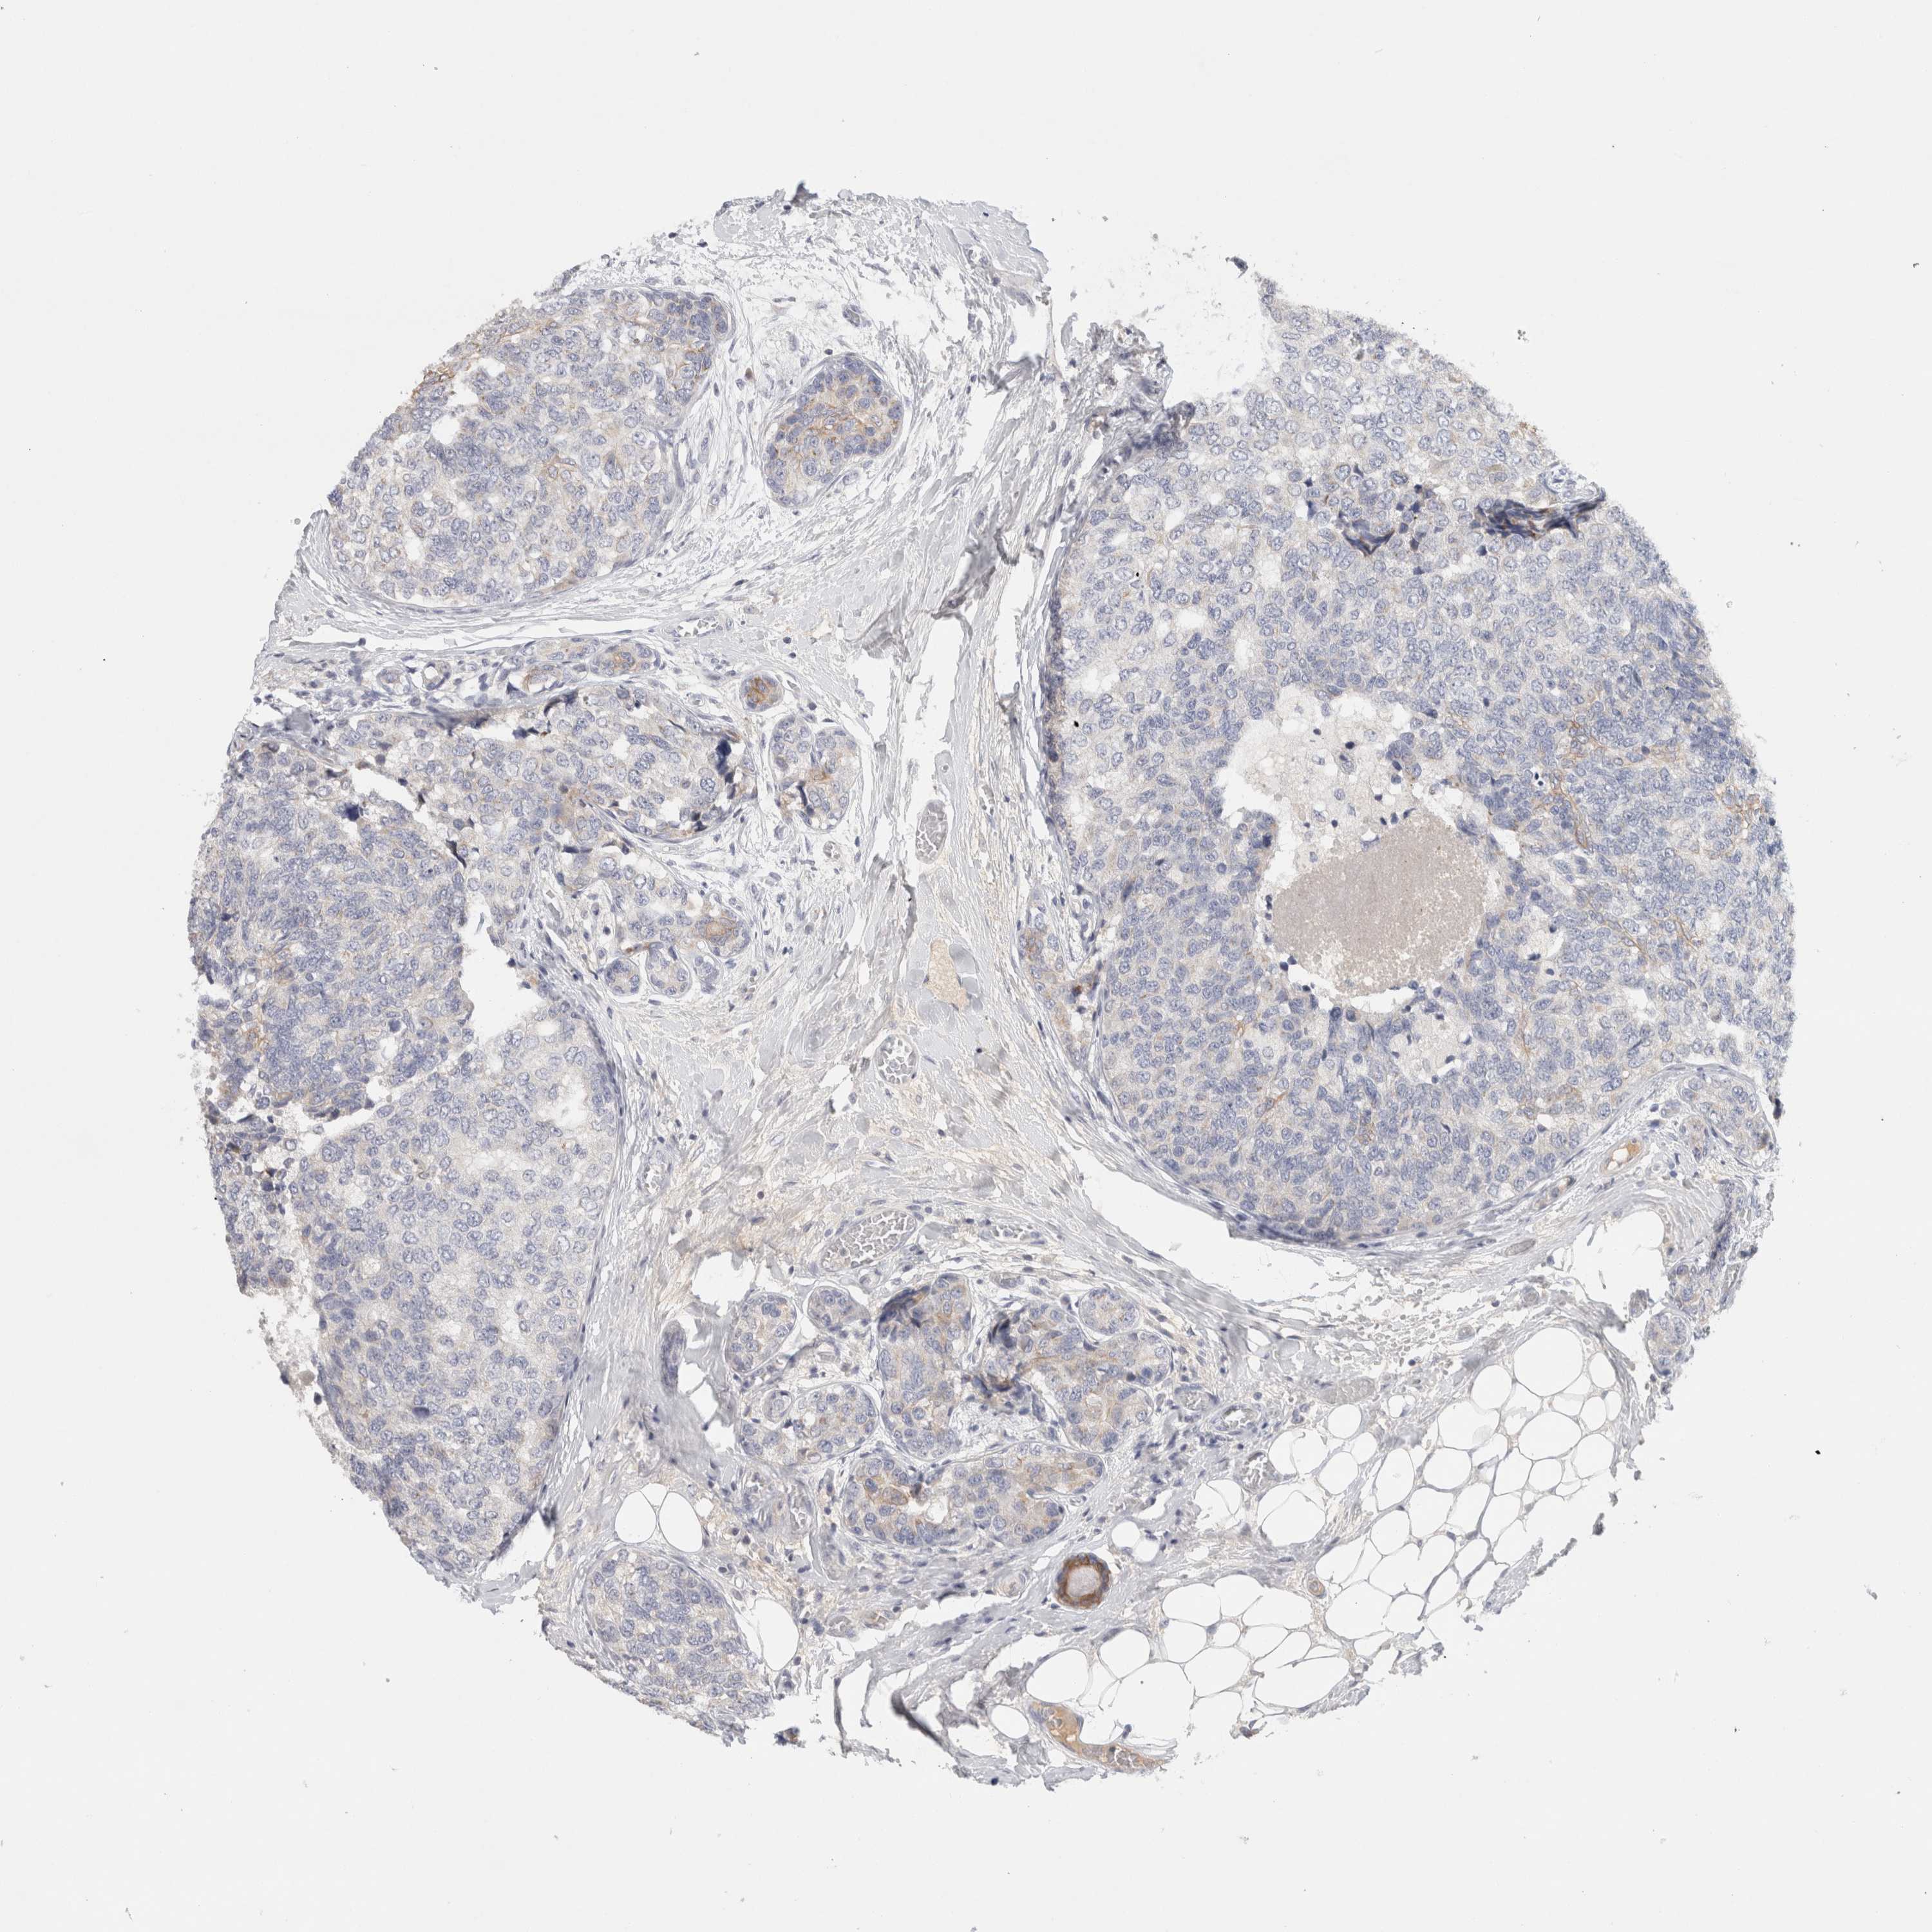

CANCER BREAST CANCER Show tissue menu

BRCA TCGA BRCA VALIDATION PROTEIN EXPRESSION

Breast cancer

Human cancer